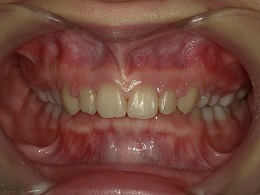

治療前正面

お試し矯正後、深い噛み合わせ改善のため上下全体矯正中の患者様の症例になります。